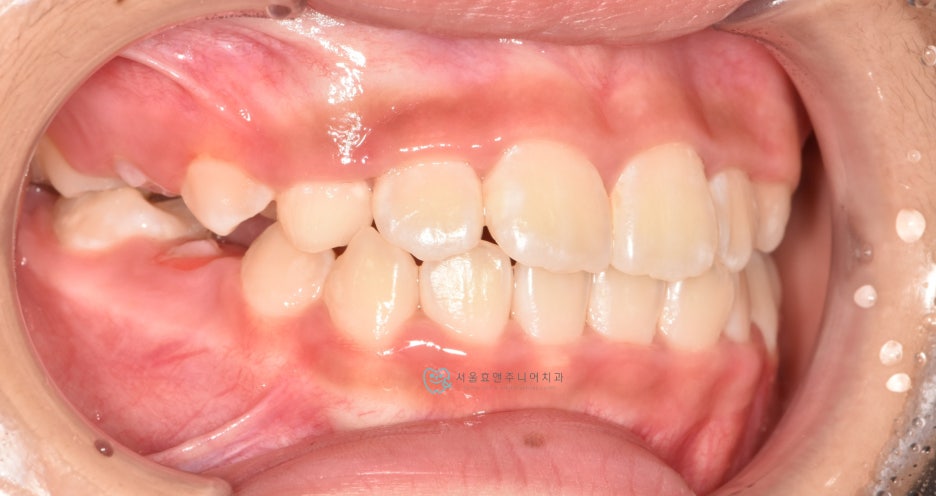

프리올소 착용 9개월 뒤

프리올소 착용 후 9개월 뒤 모습입니다. 앞니 반대교합이 수정되었습니다. 처음에 문제가 되고 있었던 아래앞니의 치은퇴축도 많이 개선되었습니다. 교합이 개선되어 치아의 위치가 바로잡히고, 치아에 무리한 힘을 더 이상 주지 않으니, 치은퇴축은 시간이 더 지나면서 점점 더 개선될 것으로 생각됩니다.